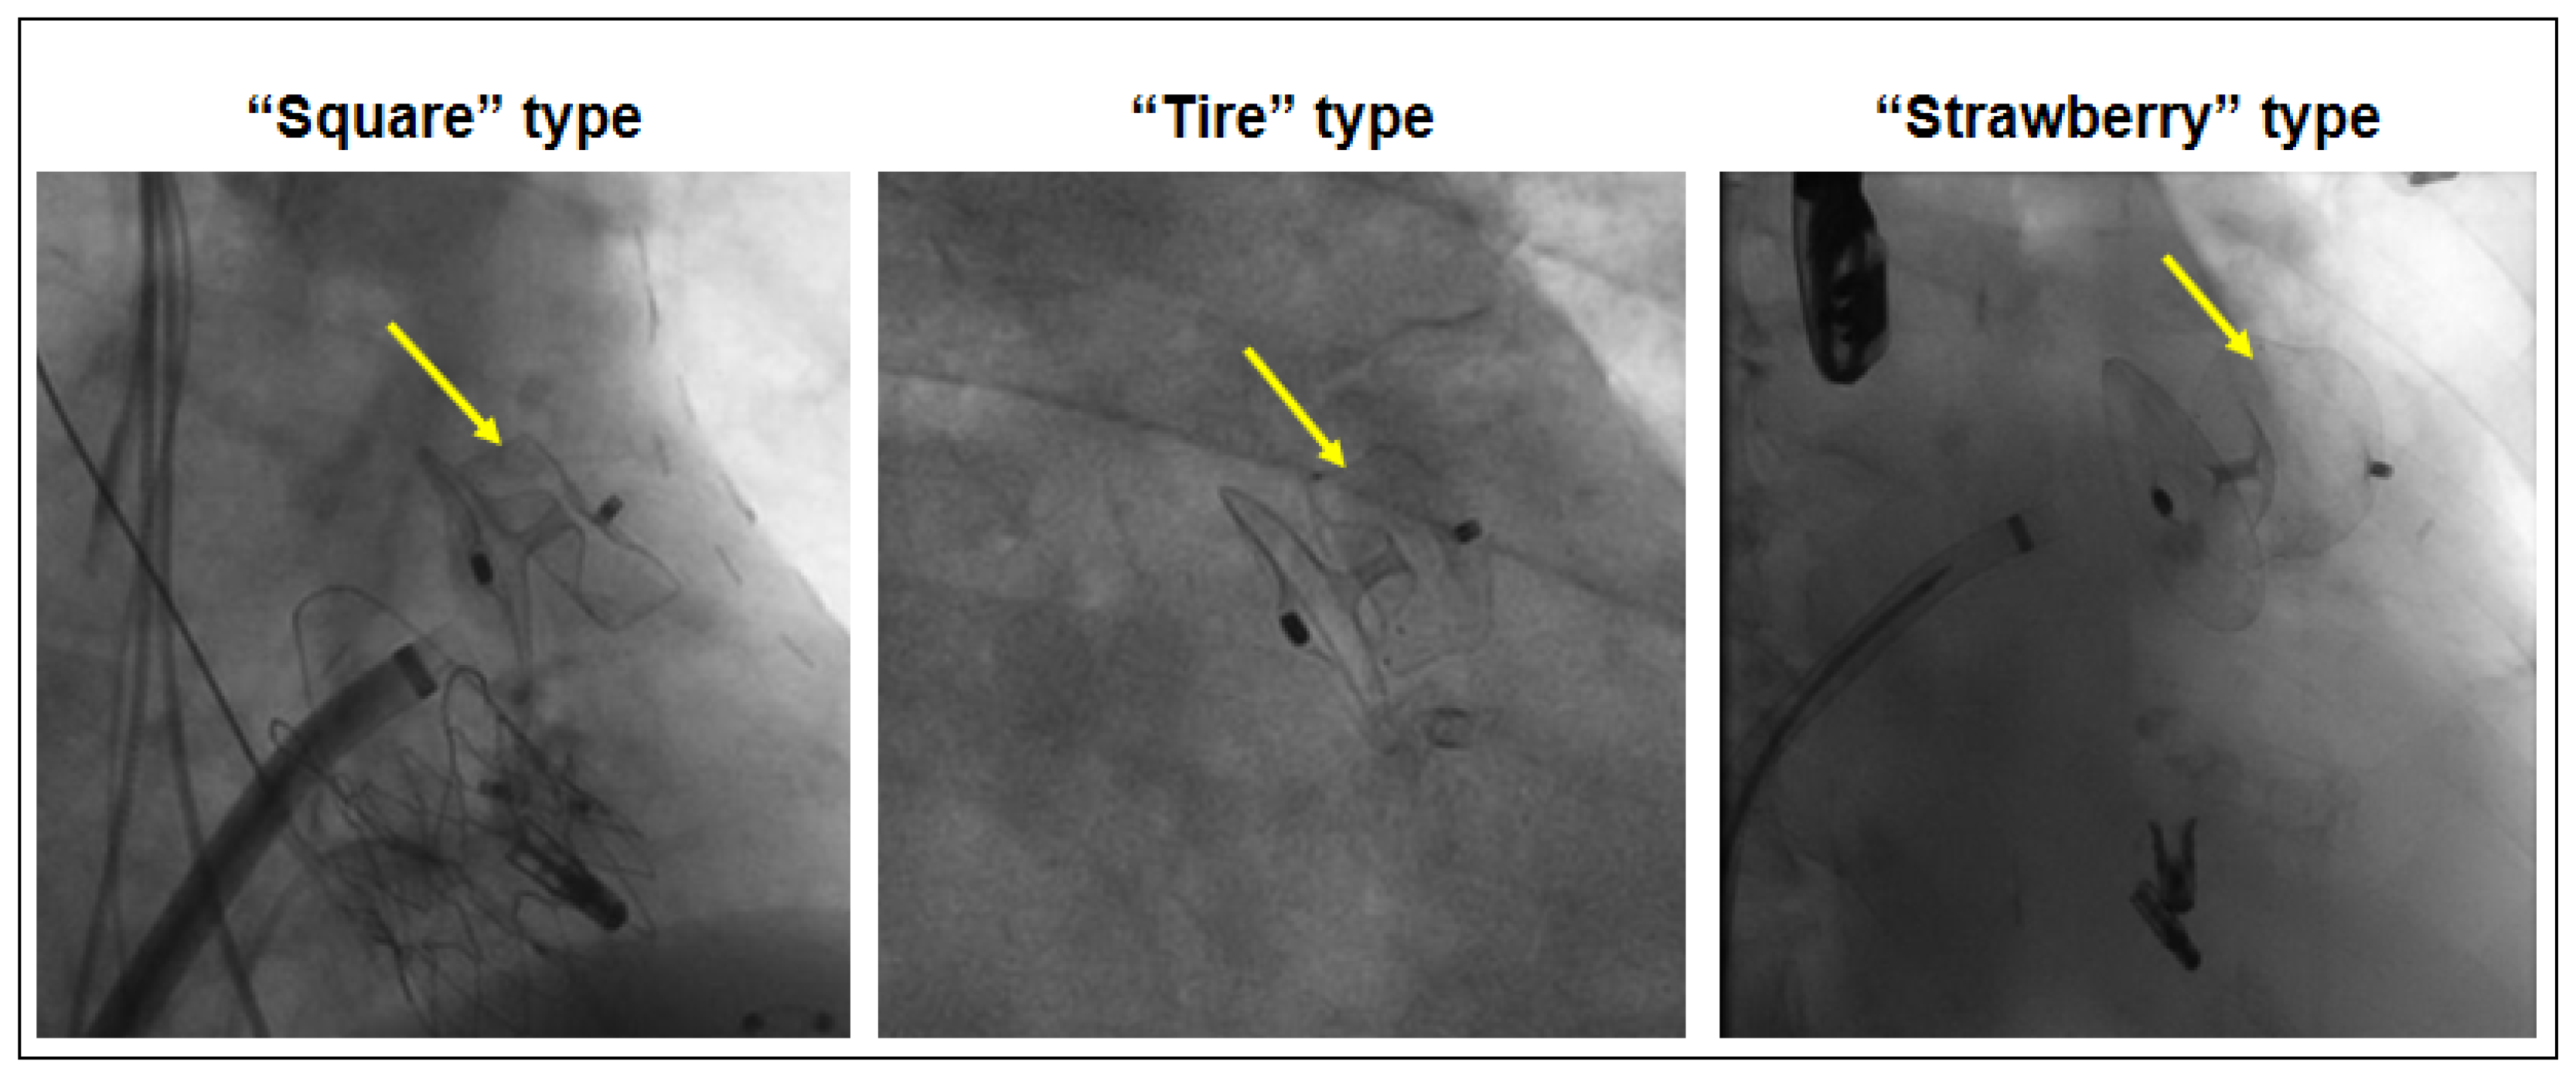

| “Square” Type (n = 9) | “Tire” Type (n = 28) | “Strawberry” Type (n = 10) | |

|---|---|---|---|

| Peri-device leak after procedure | 5 (56%) | 3 (11%) * | 3 (30%) |

| Ratio max.-min. diameter by 3D TEE | 1.35 ± 0.28 | 1.45 ± 0.17 # | |